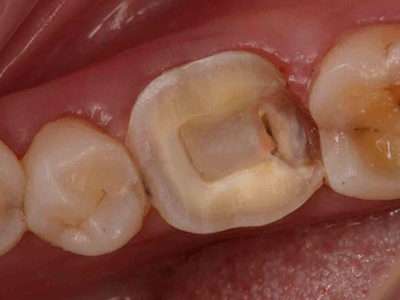

酸蚀症牙齿缺损有三角形坑洞图

酸蚀症可使牙齿发生骨质缺损,呈三角形坑洞状,位于大牙一侧,坑洞内颜色发黄,伴有局部酸涩感。该病的发生与口腔长期接触酸性物质有关。

酸蚀症牙齿缺损有凹陷图

酸蚀症患者牙齿缺损时,表现为部分骨质缺失,牙面有不规则凹陷,尤其两颗门牙病损较明显,表面凹凸不平,微微发黄,该病可能是长期大量饮用酸性饮料导致。

酸蚀症牙齿缺损有坑图

牙齿出现酸蚀症时,会有骨质缺损,牙冠表面有许多坑洼,大小不一,使之不平整,坑洞会随病情进展进一步扩大,需积极控制致病因素。

酸蚀症牙齿缺损颜色加深图

酸蚀症患者的牙齿牙冠面会出现多处缺损,下列牙齿均有不同大小的坑洞,表面坑洼不平,缺损处颜色加深,呈黄色至黑褐色,需进行牙齿修复治疗。